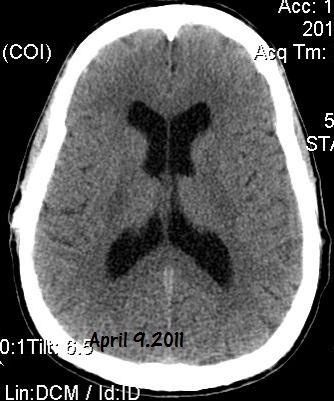

Below, are my CT images beginning on Jan. 17, 2011, where there is enlargement of the ventricles, followed by further enlargement on April 9, 2011, and what appears to be more enlargement on June 8, 2011, despite my May 23, 2011 revision. Then, there appears to be a slight decrease in ventricular enlargement on June 20, 2011, followed by normal size (almost too small) ventricles on July 23, 2011. We felt my ventricles came down in size too quickly, and began to raise the proGav setting over a period of two months, eventually up to 6, and rescanned me on Sept. 15, 2011. Those results indicated my ventricular enlargement had returned, so the proGav was returned to a lower setting of 2.

In hindsight, perhaps one mis-step we made was in not obtaining a CT scan right before surgery so as to have a true baseline. My headache, nausea, memory, and balance symptoms had worsened from April 9, 2011 to May 23, 2011, and I had lost appetite and weight. A CT on the revision date would have likely shown considerably more ventricular enlargement as compared to April 9th, rendering the post op CT of June 8, 2011, an improvement, instead of a worsening as we thought. I was having ongoing headaches upon waking in the a.m. and during the daytime after the proGAV revision, with no improvement in memory, and no apparent improvement on CT compared to April 9th, and requested that the proGAV to be lowered all the way to 0 only a few weeks post op. Despite programmable shunts having been in use since 1999, there still remains some considerable confusion and miscalculation in achieving the most optimal settings, and I remain dissatisfied with industry's inattentiveness to this issue. I also think this lack of attentiveness speaks to the high number of unofficial reports of accidental reprogramming of (Codman & Medtronic) programmable shunts. Of course, with the addition of a locking pin on the proGAV valve, this is unlikely to be an issue.

Under my CT images below, I list each of the proGAV's corresponding settings. It was initially set at 10 during surgery, with no improvement in complaints after one week, I asked that it be lowered to 7, and one week later to 5, then to 3, and finally to 0. During this period, almost every morning I awoke with a substantial headache that I assumed was due to increased ICP and underdrainage. On the June 20, 2011, CT we could finally see some decrease in the dilation of my ventricles, and determined the shunt to be working. But, we were still puzzled by the ongoing awaking a.m. headaches. For this reason, it was temporarily raised to a setting of 2, and then with no relief back down to 0. It remained at 0 for almost a month when the July 23, 2011 scan revealed normal sized ventricles.  Because of the relatively short period it took for my ventricles to come back to normal, we raised the proGAV gradually to 6, and back down to 2 after the Sept. 15, 2011 scan showed a return of ventriculomegaly.

Jan 17, 2011 OSVII                    April 9, 2011 OSVII                 Shunt Revision to proGAV May 23, 2011

June 8, 2011 proGAV  5/20    June 20, 2011 proGAV 3/20      July 23, 2011 proGAV 0/20    Sept. 15, 2011 proGav 6/20   Feb. 1, 2012 proGav 0/20